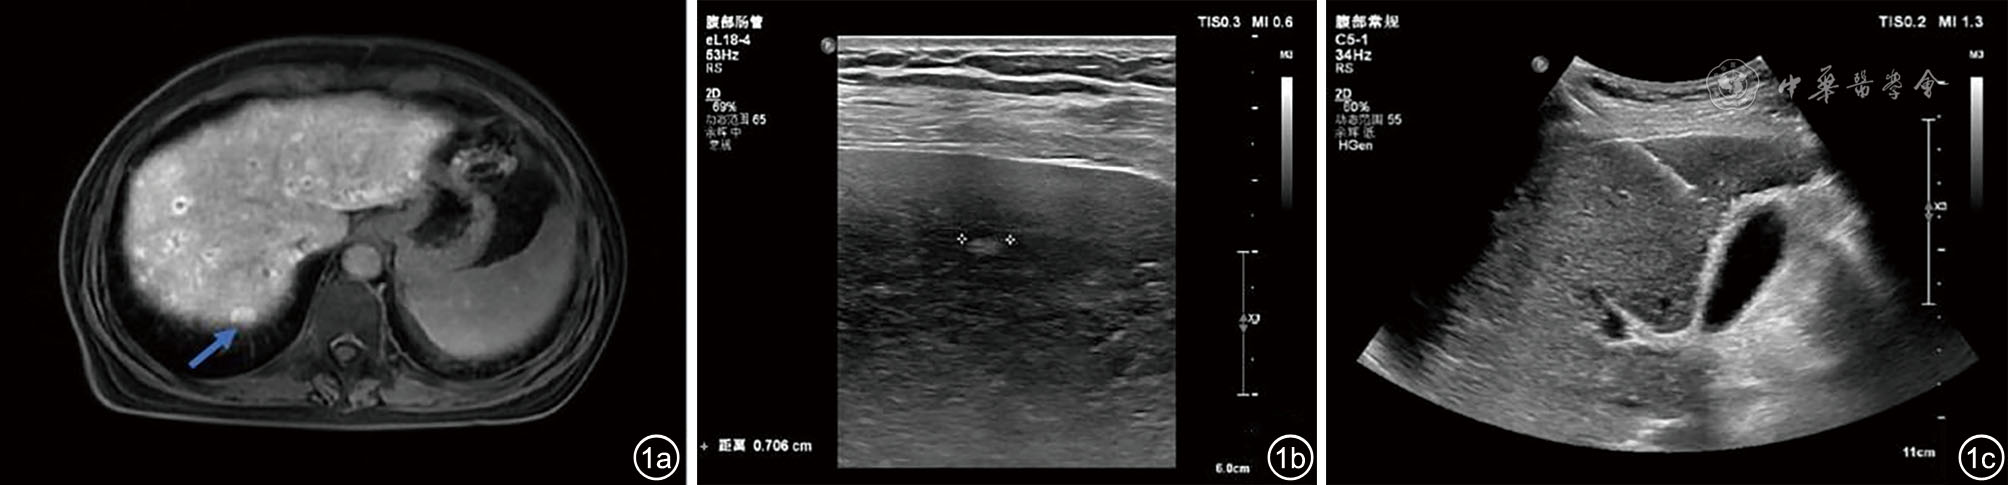

图3 经皮肝穿刺活检后上腹部平扫及增强CT图像。图a示胆囊壁增厚,胆囊腔(蓝色箭头)及胆总管(红色箭头)内高密度影,形态不规则,未见明显强化;图b示动脉期肝右前叶下段可见一过性异常强化灶(蓝色箭头),形态不规则

图4 经皮肝穿刺活检后腹部彩色多普勒超声图像。图a、b分别显示胆囊、胆总管内见高回声团块,境界清,形态欠规则,内回声欠均匀,彩色多普勒未见明显血流信号